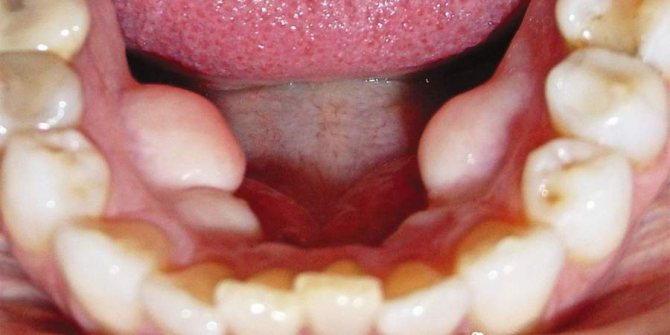

Экзостоз ротовой полости представляет собой разрастание костной и хрящевой ткани в определенном участке челюстного ряда. Визуально оно выглядит как шишка или узелок, который склонен к быстрому увеличению.

На верхней челюсти экзостозные образования чаще всего локализуются в области жевательных элементов с внешней или внутренней стороны ряды. При поражении нижней челюсти наросты формируются у основания резцов, клыков и премоляров.

- на десне прослеживается бугорок, покрытый слизистой оболочкой, которая может выглядеть неизмененной либо покрыться мелкими шипами;

- нарост увеличивается в размере и из горошины может превратиться в крупную шишку, которая вызывает дискомфорт и мешает полноценному расположению языка;

- слизистая оболочка постепенно приобретает насыщенный розовый оттенок;